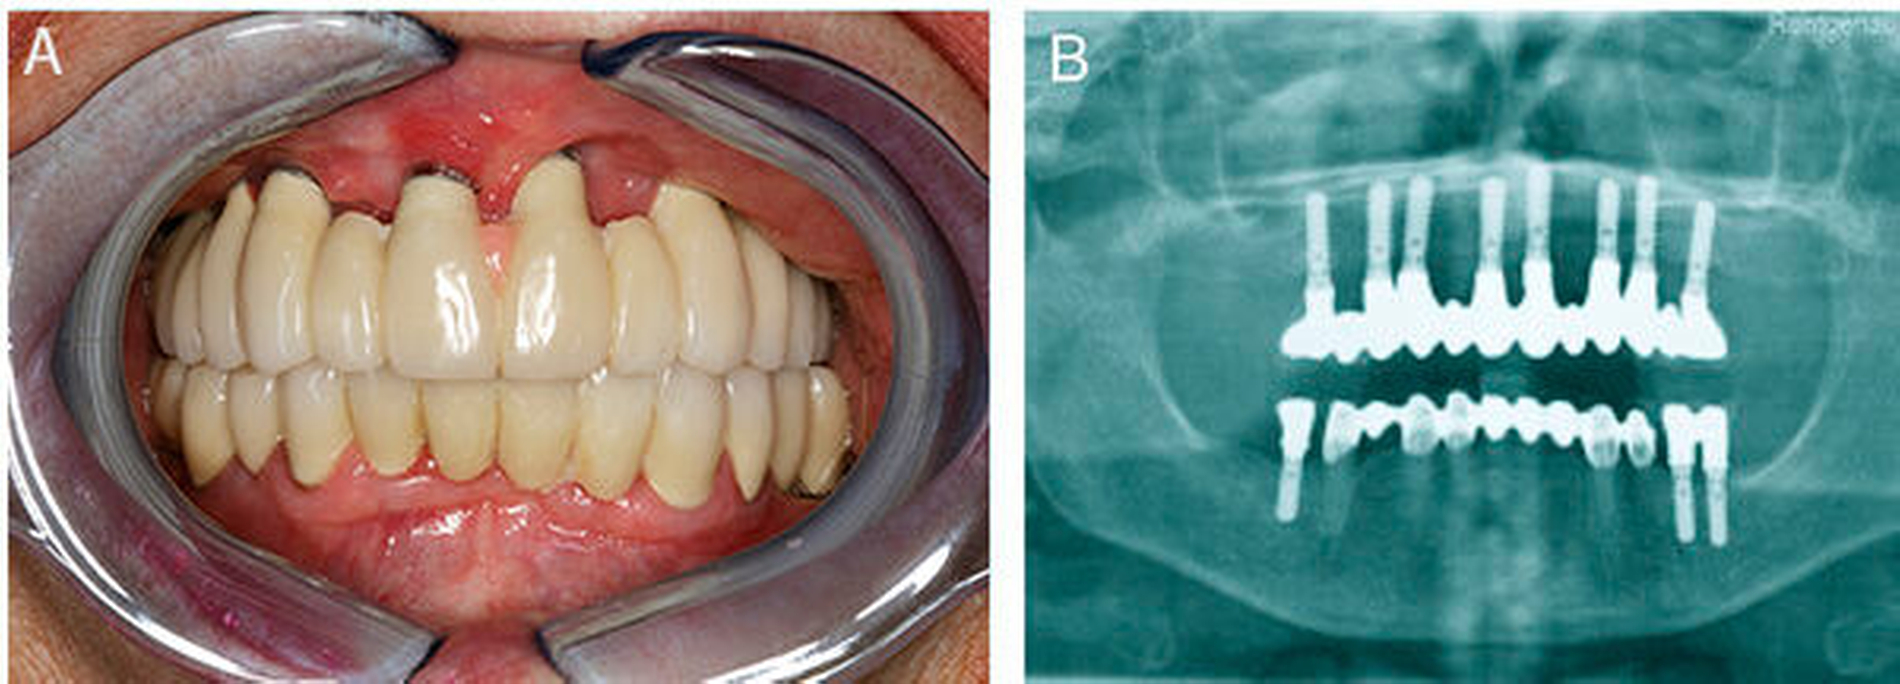

Zwischenzeitlich wurde die Symptomatik mit Hinblick auf eine allergische Genese mehrmals alio loco frustran mit Antihistaminika und Kortison therapiert. Zum klinischen Untersuchungszeitpunkt forcierte die Patientin die Entfernung der Implantate und des Knochenaugmentats. Die aktuelle Panoramaschichtaufnahme der Patientin zeigte reizfreie und gut osseointegrierte, prothetisch suffizient versorgte Implantate (Abbildung 2).